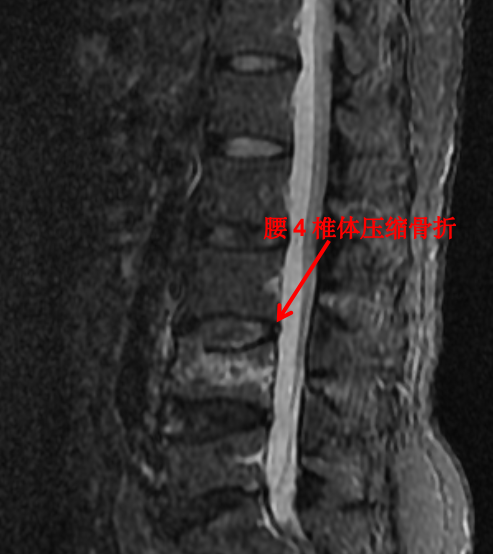

随着科技进步及医学的发展,核磁已经是脊柱外科不可或缺的检查手段。对脊柱、韧带、椎间盘、椎管内神经及椎旁组织显影都优于 CT,通过腰椎核磁我们可以直观地看到椎间盘突出的程度、神经受压的程度,以及压缩骨折的新鲜程度。

这对于脊柱疾病的治疗有着很重要的指导作用。优点是对脊柱及周围组织显影更清楚,无辐射。其缺点是价格昂贵,检查时间长,有幽闭恐惧症的患者难以接受。